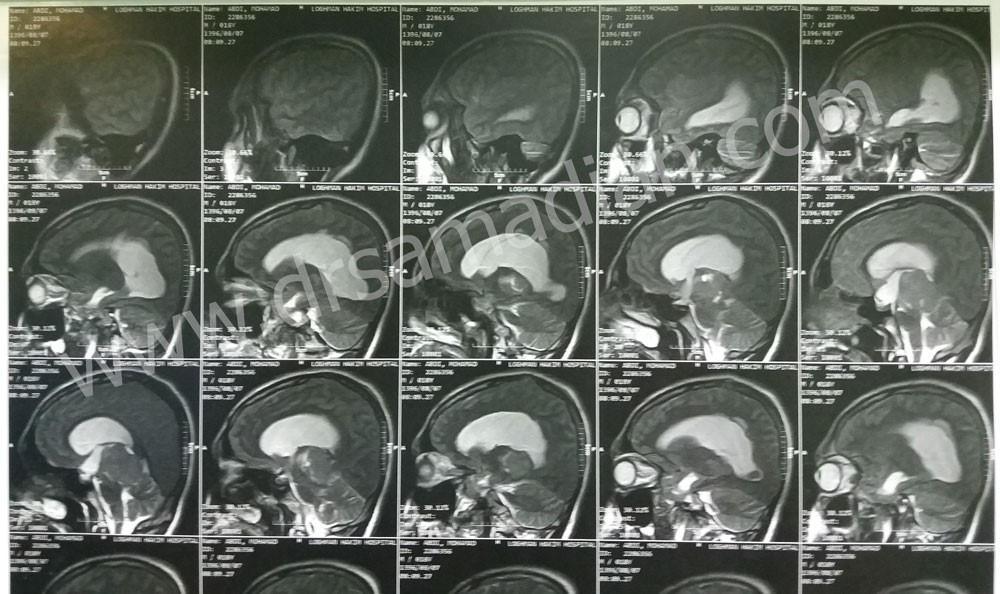

تصاویر زیر مربوط به بیمار آقای ۱۹ ساله است که با شکایت سردرد و عدم تعادل مراجعه کرده است. از حدود یک سال قبل دچار سر درد بوده است. سر درد درتمام سر منتشر شده و فشاری است . از یک هفته قبل از جراحی دچار عدم تعادل شده و یک ماه قبل دچار کاهش شنوایی شده است. هم چنین دو ماه پیش دچار تاری دید شده است . همانطور که مشاهده می کنید تومور آن توسط دکتر صمدیان خارج شده است :